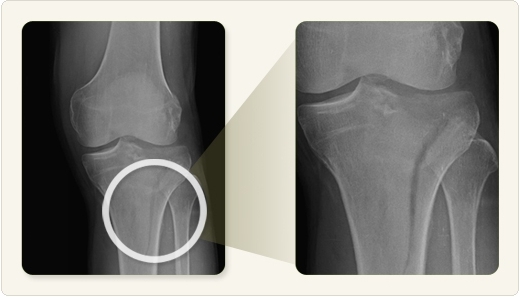

슬개골은 무릎 앞쪽에 위치한 뼈로, 강한 외상이나 낙상 등으로 골절이 발생할 수 있습니다. 수술로 고정한 이후 회복은 3개월 이상 걸릴 수 있으며, 회복 속도는 개인의 체력, 재활 순응도, 수술 방식 등에 따라 달라집니다. 최근에는 물리치료와 자가운동 프로그램을 조기부터 병행함으로써 회복을 앞당기는 사례가 늘고 있습니다. 따라서 단계별 관리가 무엇보다 중요합니다.